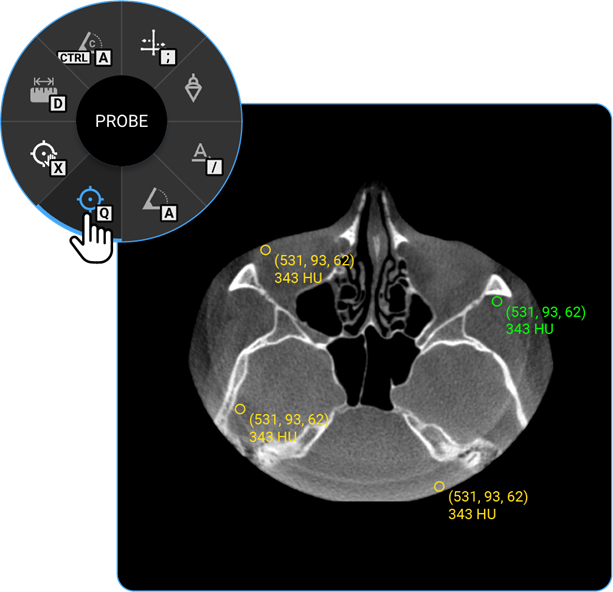

1. Drag Probe: Click on the Drag Probe tool to move a probe point across the image and assess pixel values or other parameters dynamically.

1. Probe: Select the Probe tool to analyse specific pixel values, providing information on intensity or density at a particular point.